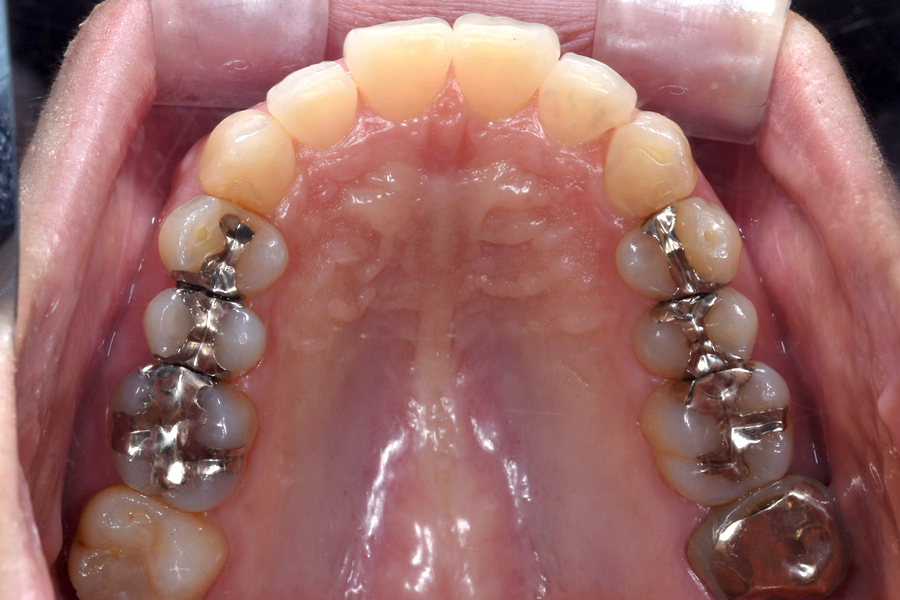

| 主訴 | 見た目を治したい、歯を白くしたい |

|---|---|

| 治療期間 | 1年6か月 |

| 治療費 | マウスピース矯正と ホームホワイトニングセット 1,022,350円(税込) |

| 治療内容 | 目立ちにくいマウスピース矯正 (非抜歯矯正) 歯と歯の間に隙間をつくることにより、歯列弓を広げながら治療を行いました。 また矯正用マウスピースをトレー代わりにし、ジェルを入れてホームホワイトニングを同時に行っております。 |

| 治療のリスク | ・後戻りする可能性があるのでリテーナーを最低でも矯正期間以上はつける必要があります。 ・ホワイトニング後、一時的に痛みが出る場合があります。 |